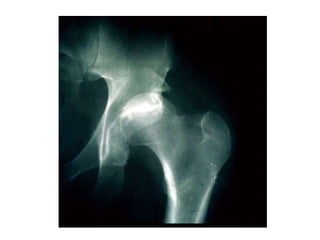

 Frederic Pauwels observed that a

curved, tubular structure under axial

load always has a compression side as

well as a tension side. Under vertical

pressure the curved femur creates a

tension force laterally and a

compression force medially A plate

positioned on the side of tensile forces

neutralizes them at the fracture site

provided there is cortical contact

opposite to this plate. In case of a

cortical defect, the plate will undergo

bending stresses and eventually fail

due to fatigue.